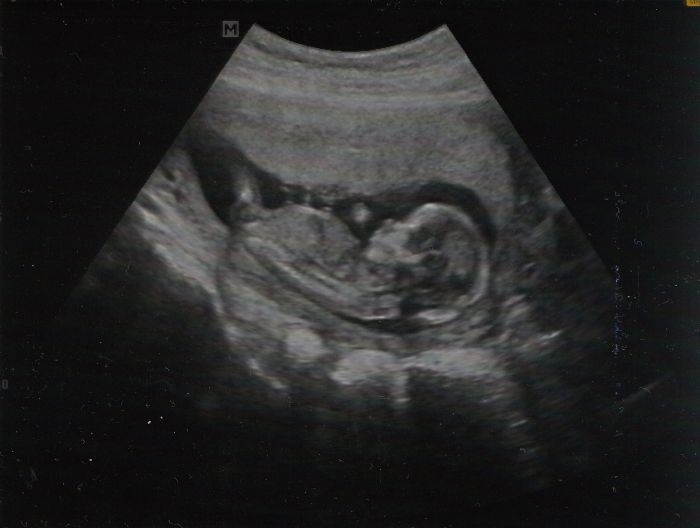

Ahoja... Zdravím všechny :) Tak dnes jsem byla na ko. Jsme 14+2. Jak jsem tak nechtě poslouchala, jsem jedna z mála, kdo nebyl na 1. screeninku... Začíná mě to trošku hlodat, ale na druhou stranu jsme s manželem mladí a zdraví, tak si říkám, že je to snad v pořádku všechno:) Příští týden jdu na odběry na tripple testy. Jsem objednaná na 13.8. a sestřička hned, jestli chci jiný datum, jestli nejsem pověrčivá :) by mi to ani nedošlo, kdyby mi to neřekla :) Tak jsem jí řekla, že echt půjdu toho 13.8., protože prcek je určo silný a zdravý :) Jinak prďola má 8 cm a paní doktorce se povedla docela pěkná fotka pro tatínka :) A prcek na UTZ neměl chybu.. Pořád sebou mrskal a ruce měl složené pod hlavičkou (takový veget:o))...

Posílám taky fotku ze včerejšího screeningu :-) dnes jsem teda 13+0, oznámila jsem to v práci, tak to většina tak čekali, někdo byl překvapenej :-)